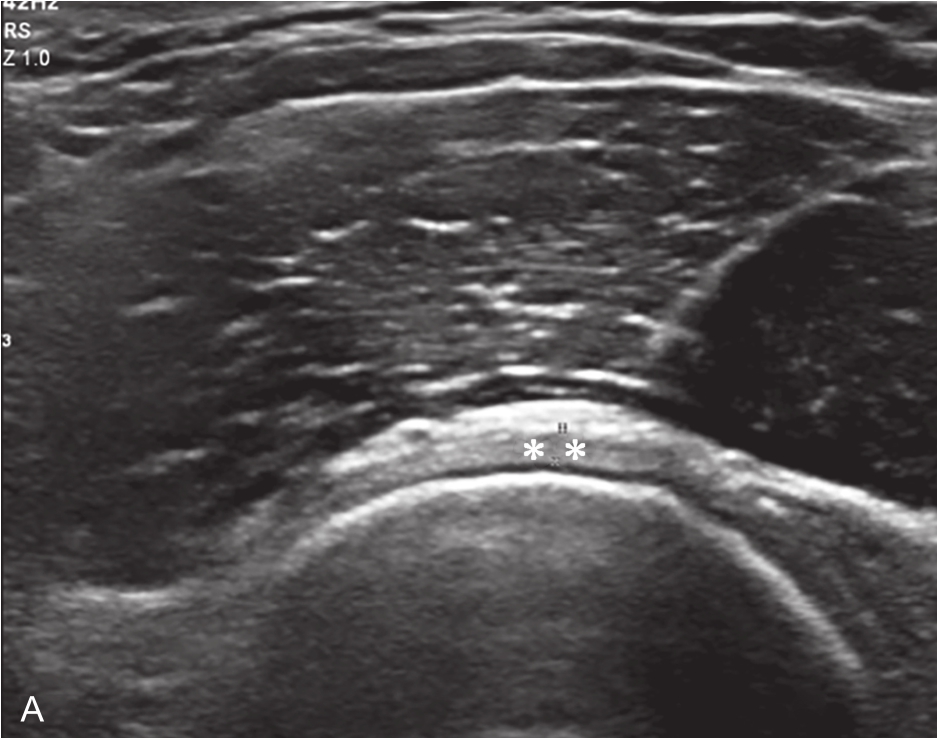

▲ 图2-6-3 超声引导下肩关节腔介入治疗超声图(一)

A、B.二维超声显示肩关节腔少量积液,滑膜增厚;C.超声引导针尖进入关节腔;D.超声示意图,虚线蓝色区域:后关节腔;单星号:腋下关节囊;双星号:后关节腔;短箭头:穿刺针;长箭头:穿刺针路径;L:盂唇;HH:肱骨头